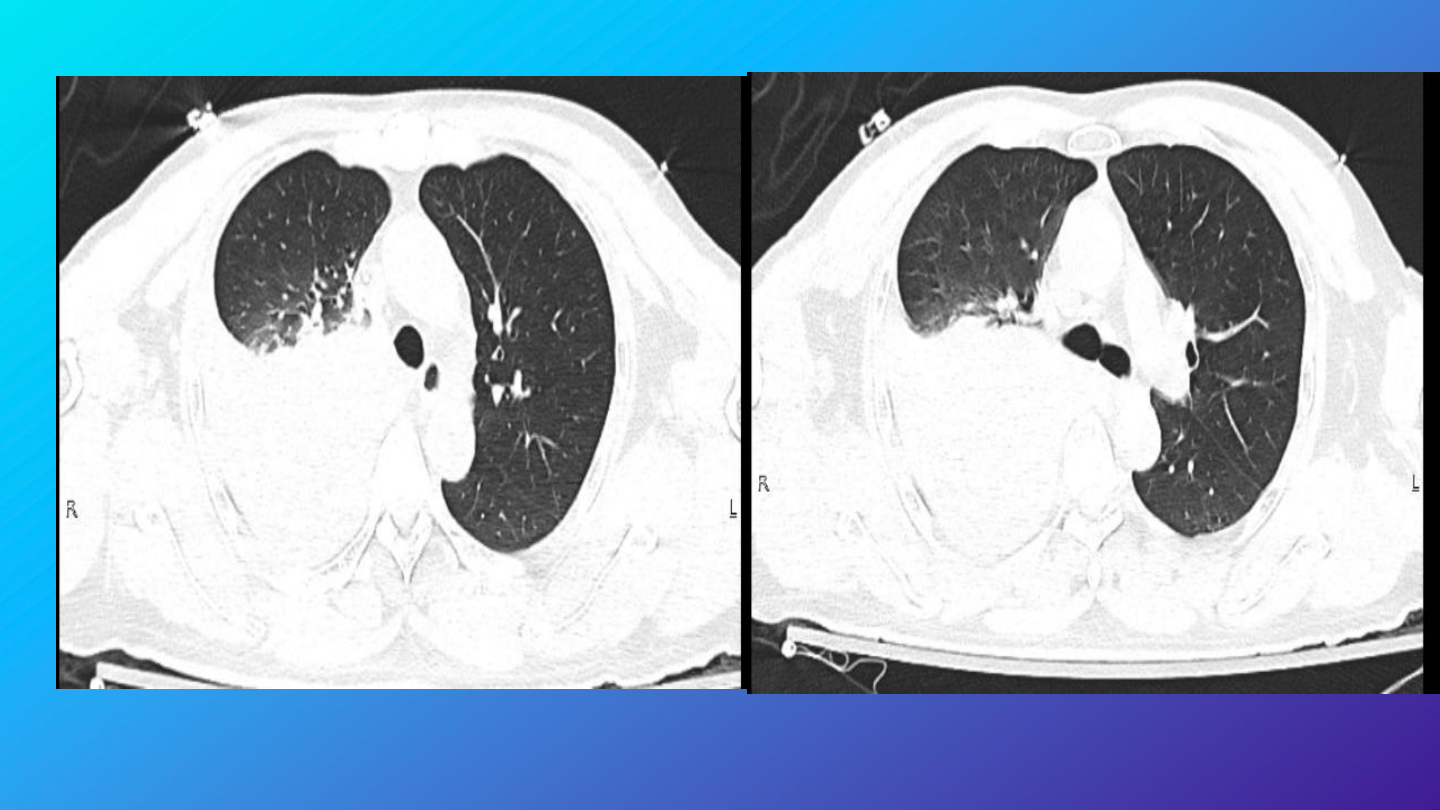

急诊完善胸腹部

CT

检查

结果:

右肺中下叶及左肺下叶炎性渗出,右侧胸腔

积液,建议治疗后复查。

左肺各叶数枚良性小结节及钙化灶。

右侧第

6

肋骨骨皮质褶皱。

肝内数枚囊肿。右侧腹股沟管增宽,部分脂

肪疝出。